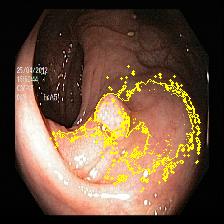

Figure 5 showcases paired examples of raw and LIME-explained images across various classes, providing direct comparisons and highlighting the influence of visual enhancements on the interpretability of the model.

![]() |

| (a) | (b) | (c) | (d) |

LIME Parameters

For this study, the parameters of LIME are carefully configured to provide meaningful and interpretable insights into the classification decisions made by our endoscopic image classification model. To generate robust local explanations, the number of samples parameter is set to 1000, ensuring the creation of a sufficient number of perturbed samples around the input instance for accurate approximation.

To highlight the most informative image segments, the positive contributions only parameter is set to True, focusing solely on those superpixels that contributed positively to the predicted label. The number of features parameter is set to 5, limiting the explanation to the five most critical superpixels for interpretability. Additionally, the color to hide irrelevant regions parameter is assigned a value of 0, using a uniform black color to obscure non-relevant regions in the image during the explanation process. Finally, the minimum weight threshold parameter is set to 0, ensuring that all superpixels with weights above zero are included in the explanation.

The findings confirm LIME’s effectiveness in shedding light on the model’s decision-making process for both standard and dyed endoscopic images. With LIME generating visual explanations, clinicians can better understand the regions that influence the model’s predictions, thereby gaining insight into how visual enhancements guide the AI’s focus.